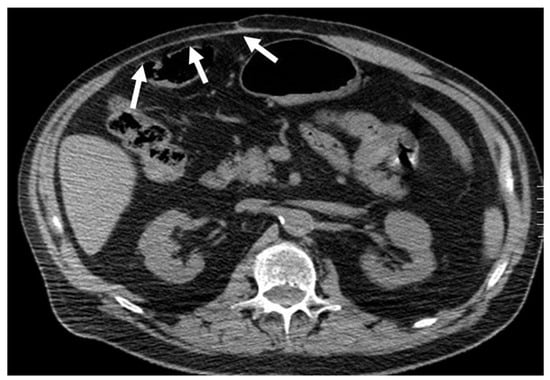

Abdominal wall abscesses present on US as superficial fluid-filled complex lesions, with ill-defined margins, predominantly hypoechoic to surrounding muscles [7,8]. Peripheral hyperemia can be seen on Color Doppler US (CDUS) [3] (Figure 1). To define the extent of the abscess, contrast-enhanced CT and MR could be used in severe cases.

Figure 1. Abscesses on US and CT in a 69-year-old woman with myelofibrosis, presenting with pain along the surgical scar and persistent fever two weeks after splenectomy. B-mode US (first picture, arrow) demonstrates a fluid collection, with no significant vascularization on color Doppler (CD, lower picture). On portal-phase CT (third picture), the abscess is easily distinguishable (arrowhead).